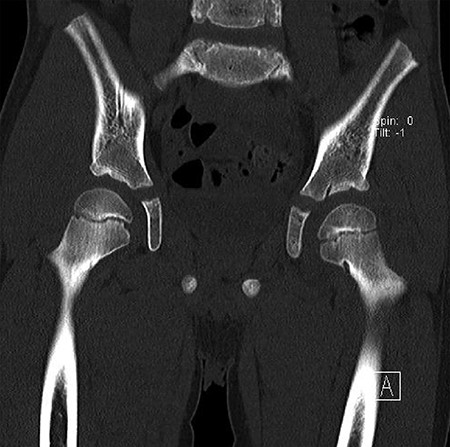

CT hips reported a well-defined lesion seen bilaterally in the neck of femur anterior infero-medial aspect, more prominent on the left side measuring 7 x 3 mm on left side both in coronal (Fig. 3) and axial (Fig. 4) views. On the right side, other lesion measuring 2 x 1 mm (Fig. 5) seen in coronal view. These two lesions are well defined with a sclerotic border with a small cortical defect. The lesion shows fat density. The symmetrical appearance of the lesion combined with the fat density and location suggest the diagnosis of synovial herniation pit. MRI Pelvis revealed minimal left hip joint effusion with loculated fluid seen along the trochanteric bursa with the largest measuring 0.9 x 1.5 cm (Fig. 6, 7).

Showed axial cut of CT hips demonstrating the synovial pit on left and right side.